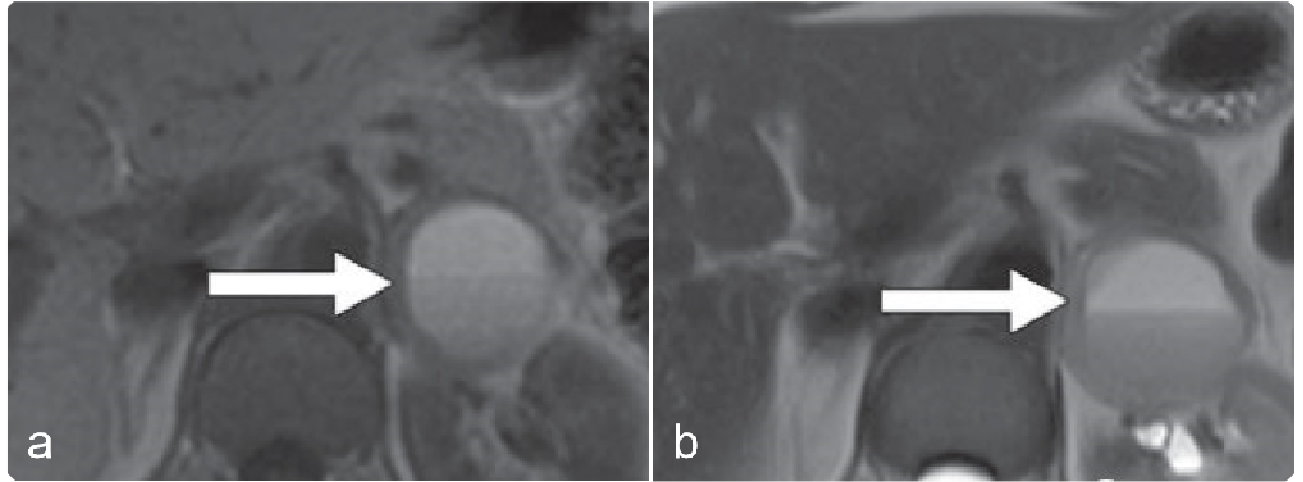

肿瘤边界清楚,平扫较均匀的低密度,低于肌肉,20%~30%的病例可有斑点状或针尖样钙化。匍匐性生长,呈爬行生长或沿器官间隙呈嵌入方式生长,容易形成伪足样改变,不侵犯周围组织及血管。

动脉期无明显强化,静脉期和延迟期有渐进性轻度强化,延迟强化的原因主要是由于肿瘤细胞外间隙内大量的黏液基质阻碍造影剂的灌注;不均质,T1WI呈均匀低信号,T2WI呈显著高信号,可见“螺旋状”的黏液样基质。

病例示例:

2b187c6c66f824726ee9fd9bfcae4cbf.png 病例 30:(右侧肾上腺区)节细胞神经瘤1例瘤体边界清楚,平扫呈均匀低密度,低于肌肉,呈嵌入式生长,动脉期瘤体无明显强化,壁呈轻度强化,静脉期和延迟期可见渐进性强化,冠状位瘤内可见血管影,未见明显受侵。

ac363d5af64c789e6803554f114ed8be.png 病例 31:(左侧肾上腺区)节细胞神经瘤  39岁男性,偶然发现左侧肾上肿块(a) T2WI显示螺旋状外观,高信号的粘液样基质及低信号的曲线带(箭头)。(b) 明显外周强化。(c) 大体病理显示肿块边界清晰,切面呈胶状棕褐色,局灶性出血。(d) 镜下显示纺锤形雪旺氏细胞(*)与神经节细胞(箭头)混合在胶原基质中(HE×100)。